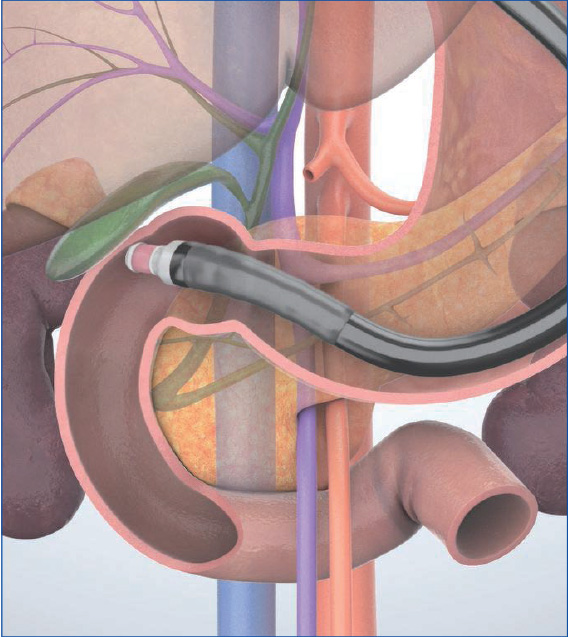

Imaging Techniques Trans-D1 (duodenal bulb) approach

In the “long-scope” position from the duodenal bulb, observe the extrahepatic bile duct as well as the pancreatic head, gallbladder, and cystic duct. Advance the scope from the duodenal bulb to the descending part’ to observe the pancreatic head and the vicinity of the duodenal papilla. It is difficult, however, to image the duodenal papilla and the lower part of the head of the pancreas in this scope position. Switch to the “short-scope” position to observe them. Since there is a risk of perforation, it is important to avoid forcible scope manipulation.

Understanding the anatomy when scanning in the trans-D1 (duodenal bulb) approach (“long-scope” position)

When you start scanning in a position at the superior duodenal angle (SDA) once the scope tip has passed the pylorus, it is relatively easy to visualize the portal vein and the bile duct in a long axis. The reason the bile duct is visualized in a long axis in this position is because the duodenum is located in the retroperitoneal space, so the tip of the transducer points to the dorsal side from the ventral side when inserting the scope (Fig. a). At this point, the descending part of the duodenum viewed downward from the SDA appears in the endoscopic view (Fig. b). When the scope tip points to the feet of the patient and is bent up, the long-axis view of the bile duct is imaged to the left of the transducer (Fig. c).

When the scope is further advanced past the SDA, the aorta and the inferior vena cava are visualized on the short axis instead of the long axis due to the change in transducer position, which is now being directed towards the patient’s feet instead of their back. (Fig. d). You can surmise the position and the shape of the scope in the duodenum from the way that the aorta and the inferior vena cava are visualized.